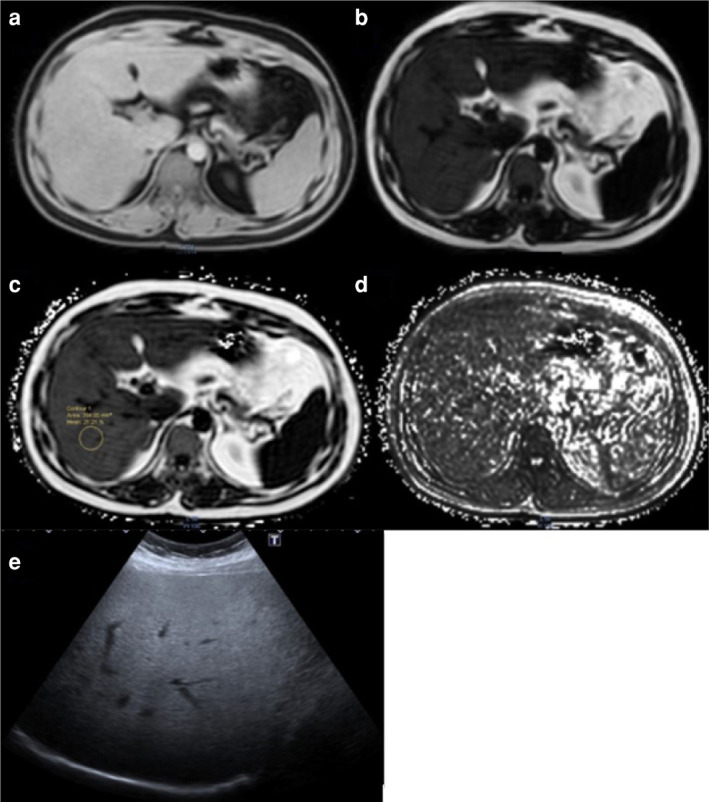

Background and aim: To investigate the relationship between ultrasonography (US) and magnetic resonance (MR) proton density fat fraction (PDFF) techniques, using the modified DIXON method, in determining the severity of liver steatosis.

Materials and methods: This study included seventy consecutive patients who underwent upper abdominal MRI for various reasons between June 2016 and January 2017. Fatty liver staging was performed using US as indicated.The liver fat percentage was measured and staged according to PDFF values.

Results: In the study, of the 70 cases, 36 were male and 34 were female. On US, 18.5% of the cases had stage 0, 32.8% had stage 1, 42.8% had stage 2, and 5.7% had stage 3 liver steatosis. A significant correlation was found between ultrasonographic evaluation and PDFF in determining the percentage of liver fat (r=0.775, p<0.001). When comparing the percentages, MR-evaluated PDFF and ultrasonographic staging were most compatible at grade 3 and least compatible at grade 2. When the PDFF threshold value was set at 8.1%, the sensitivity of US in distinguishing between obvious and indistinct steatosis was 97.1%, and the specificity was 88.9%.

Conclusion: Ultrasound continues to be a useful tool for detecting fatty liver disease. However, magnetic resonance (MR) proton density fat fraction (PDFF) imaging is essential for accurately determining the severity and prevalence of steatosis. Our study revealed inconsistencies between US and MR PDFF in grading liver steatosis, showing higher agreement in severe cases and lower agreement in moderate cases. Therefore, we recommend classifying steatosis as either uncertain or apparent rather than using a grading system in US.